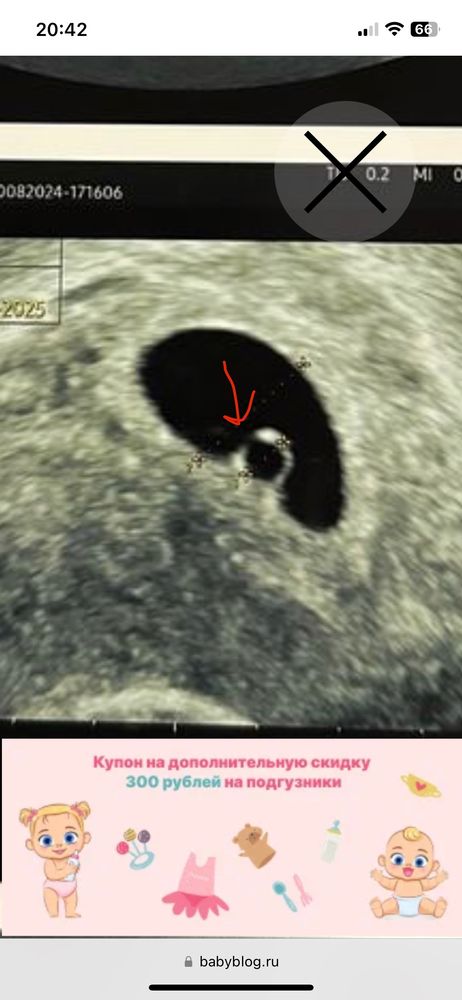

Ксюня, так обычно называют эмбрион на раннем сроке беременности. Эмбрион бриллиант, а желточный мешочек само колечко)) а все вместе выглядит как колечко с бриллиантом))) Изображение

Ксюня, вот тут появится) ждите ❤️ Изображение